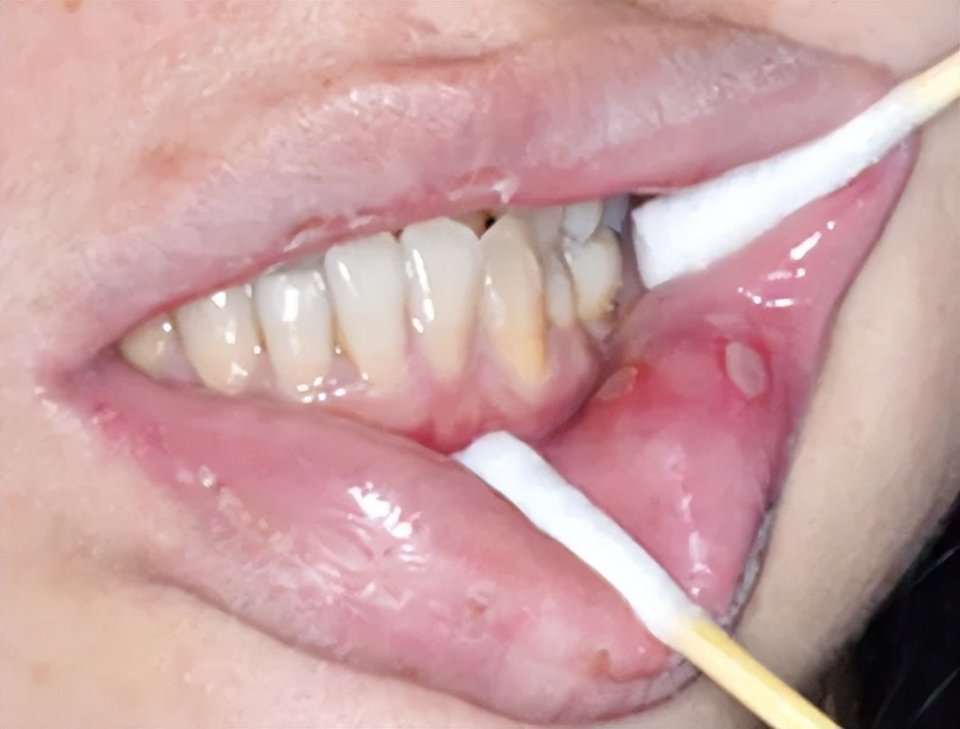

若患者表现为口干、黏液囊肿、黏膜萎缩、溃疡及假膜等症状,而无特征性改变,则需排除药物、感染、肿瘤等原因,并辅助组织病理学检查以明确诊断。

cGVHD口腔表现:红斑、苔藓样损害、溃疡及假膜形成(图片源自陶人川教授团队)

口干表现(图片源自陶人川教授团队)